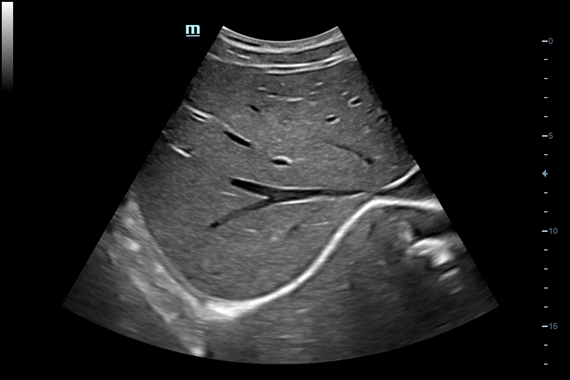

Система ультразвукового исследования Mindray DC-60 EXP X-INSIGHT является новейшей разработкой для проведения комплексных обследований на высшем уровне. Она обеспечивает решение самых сложных задач в таких областях, как кардиология, акушерство и гинекология, сосудистые заболевания, педиатрия и многие другие.

DC-60 EXP X-INSIGHT - это современный стационарный УЗИ-аппарат с функцией сенсорного управления и очищенной гармонической визуализацией, обеспечивающей лучшее контрастное разрешение и технологию 4D-визуализации. Он оснащен 21,5-дюймовым монитором, который может поворачиваться на 180 градусов, что удовлетворяет потребности врачей в качественной ультразвуковой диагностике.

• Smart OB™ - программа автоматического расчета с возможностью ручного редактирования основных акушерских показателей: БПР, ДБ, ОГ, ЛЗР, с использованием алгоритмов автоматического оконтуривания и распознавания границ органов

• Smart NT - программа для автоматического определения и расчета толщины воротникового пространства у плода